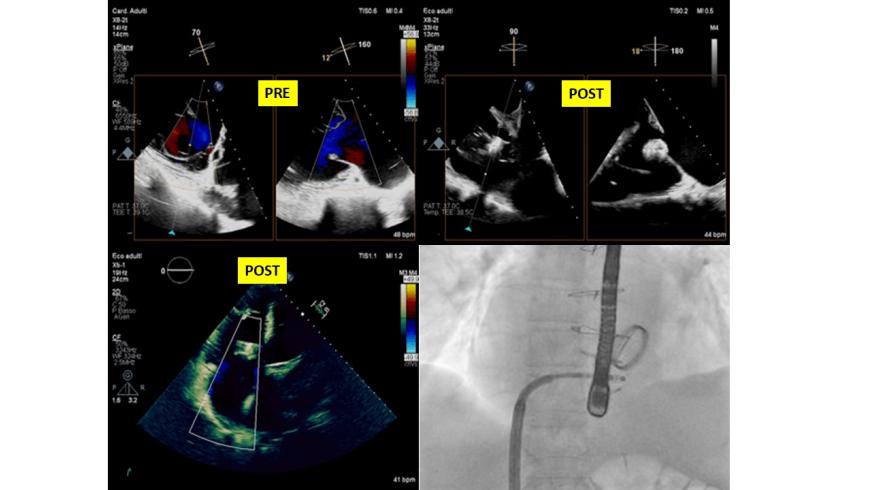

All'AOU di Novara varata la tecnica "Sandokan" per curare l'insufficienza tricuspidalica

L'équipe di Cardiologia Interventistica dell'Azienda ospedaliero-universitaria "Maggiore della Carità" di Novara, guidata dal professor Giuseppe Patti, ha sperimentato con successo una nuova tecnica per il trattamento dell'insufficienza tricuspidalica.

Tecnica Sandokan